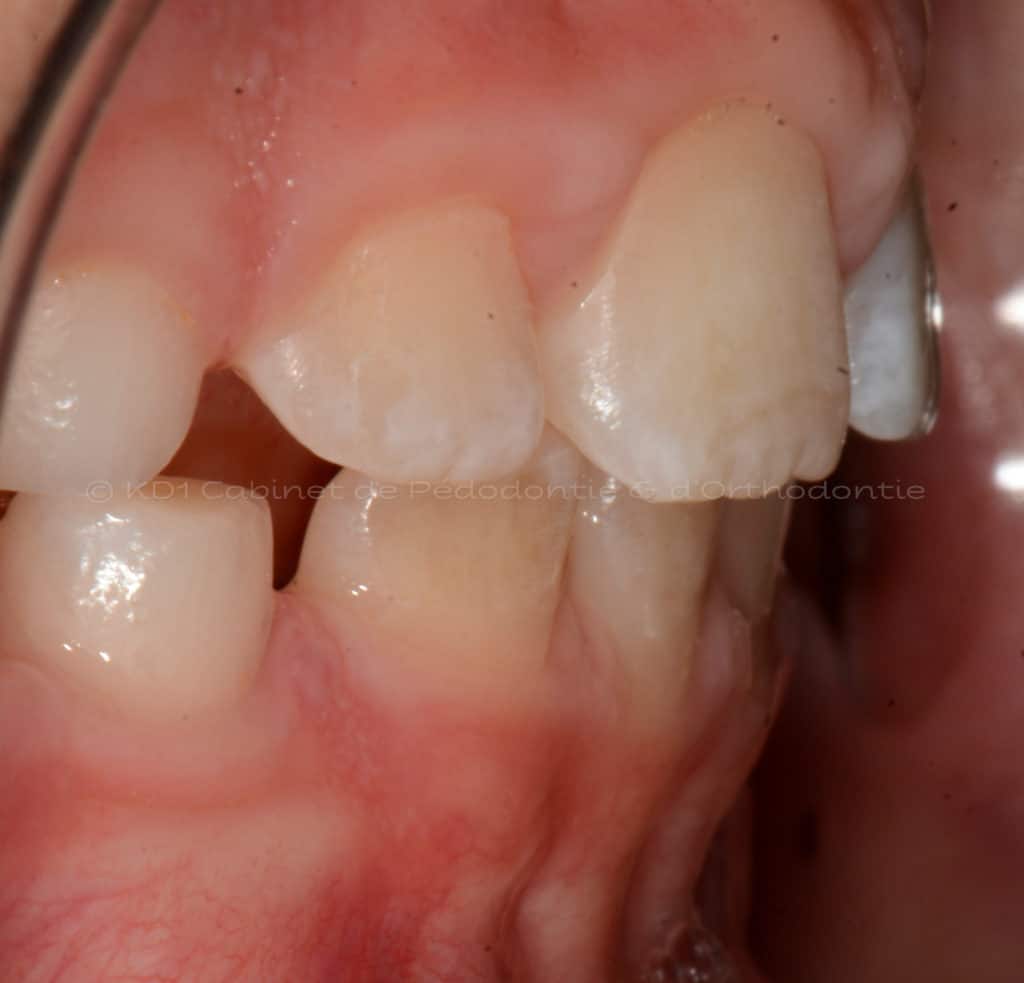

Correction des problèmes d’occlusion en dentition mixte, c.-à-d. à l’âge où l’enfant a des dents de lait et adulte, souvent entre l’âge de 7 ans et 9.5 ans. Le but de ces interventions n’est pas d’aligner les dents, car la dentition est en train de changer.

Cas #3 – Traitement avec un casque de traction maxillaire en dentition mixte (âge 9.5). Le but est de redresser les dents de devant (très penchées en avant) afin d’éviter les cassures de ces dents. Le recul de la dentition supérieure est possible avec ce dispositif extraoral. Un effet favorable indirect sur la mâchoire inférieure est à visible.